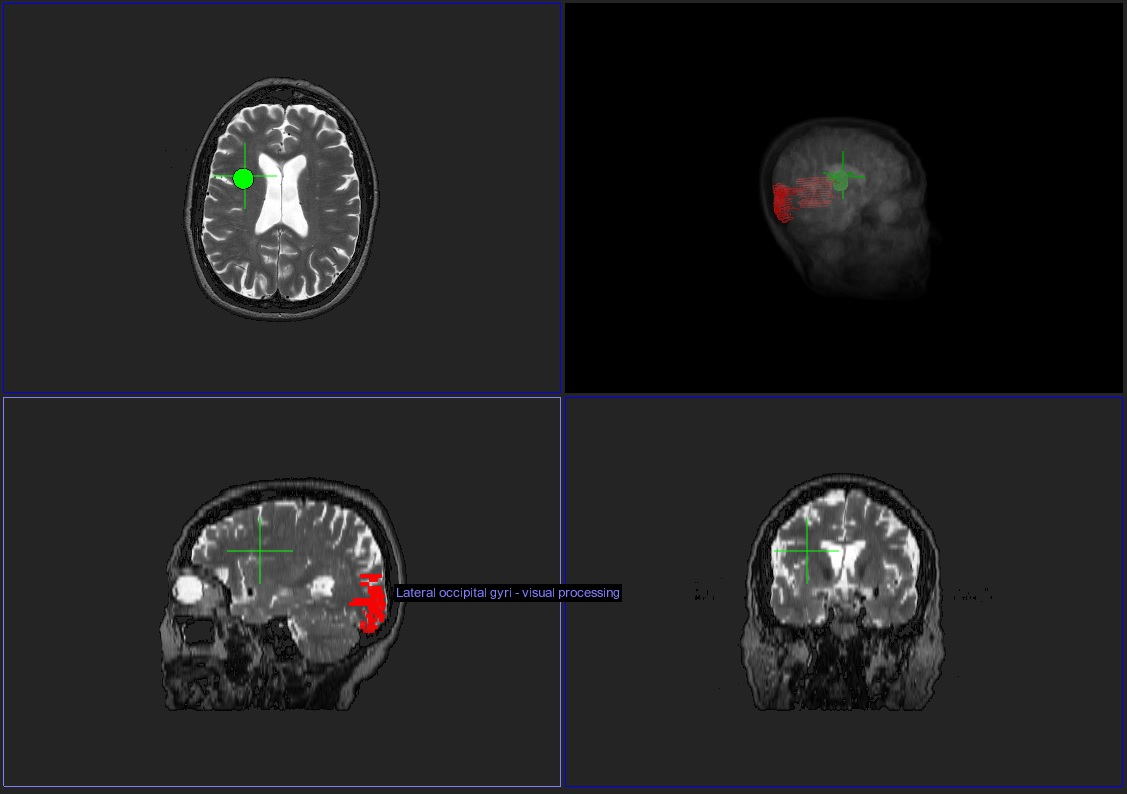

There is risk in directly treating tumors of the central nervous system through surgery. To guarantee total removal may require marginal invasion into surrounding tissue, resulting in possible neurological deficits, and subtotal surgery may result in a recurrent mass. The software system Anatom-e (Anatom-e Information Systems, Houston, TX) utilizes a database of nervous system tracts and structures to identify the regions surrounding the tumor, accesses their functions, and provides a list of potential signs as a result of surgery allowing for informed medical decisions and educated patient choices. The software uses a platform known as a deformable anatomic template (DAT), which is the nervous system and its structures overlaid onto an existing scan of normal status. Patient data is uploaded ranging from CT to MR body and brain scans, and aligned with this existing image set. The DAT then morphs to match the patient data, resulting in a neurological map of pathways and tracts that fit uniquely to the patient. Built-in software tools can be used to gather information on regions of interest, or analyze the proximity of structures to a particular site. The implications of Anatom-e range from pre-surgical planning and radiation therapy to intra-operative navigation. This project aims to utilize retrospective analysis to match real cases, surgeries and their outcomes to the predictions, insights, and information provided by Anatom-e, and the results from this study can aid in software development and direction.